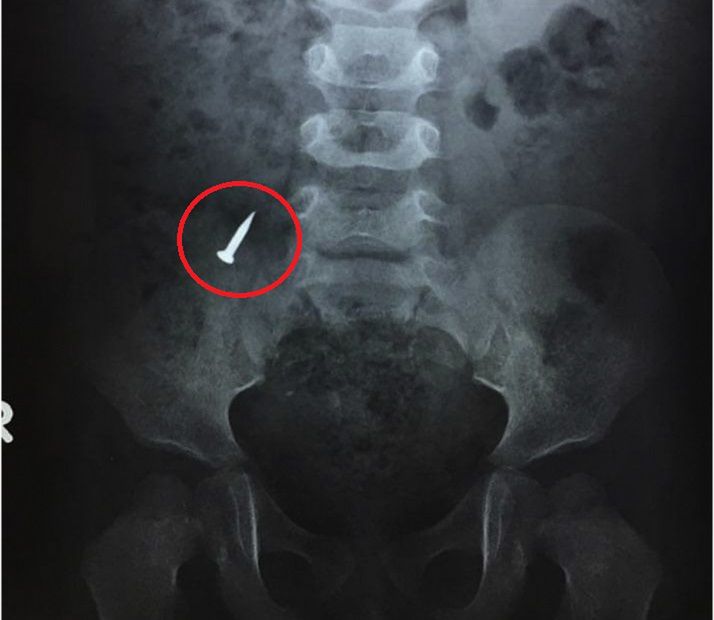

Dziecko trafiło na izbę przyjęć. Lekarze wykonali badanie RTG, które potwierdziło obecność połkniętego przedmiotu w brzuchu.

Zdjęcie RTG jamy brzusznej chłopca

Zdjęcie RTG jamy brzusznej chłopca © Facebook

Czterolatek wymiotował i skarżył się na ból w prawym dole biodrowym. To właśnie w tej okolicy, zgodnie ze zdjęciem RTG, utkwił połknięty gwóźdź. Miał też podwyższony poziom białych krwinek.